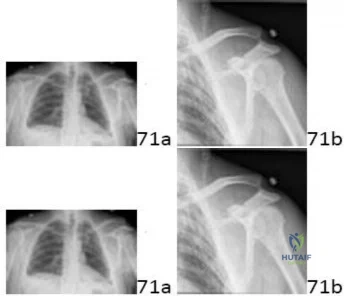

A 22-year-old overhead throwing athlete complains of deep shoulder pain during the late cocking phase of throwing. MR arthrography reveals a Type II Superior Labrum Anterior to Posterior (SLAP) tear. Which of the following best describes the specific anatomical pathology of a Type II SLAP lesion?